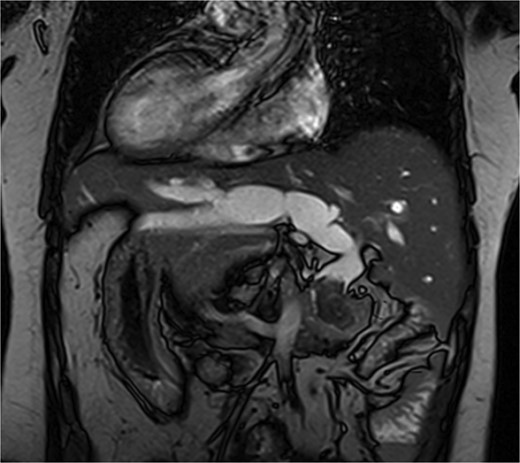

The patient, a 56-year-old female, was admitted on July 7, 2024, with a one-day history of abdominal pain and fever. The pain, which began on July 6 after consuming greasy food, was paroxysmal and located in the upper abdomen, accompanied by chills and a fever as high as 39°C. CT imaging revealed common bile duct stones and post-cholecystectomy status. Physical examination upon admission showed jaundice, with mild tenderness in the left upper quadrant, without rebound tenderness, and a negative Murphy’s sign. MRI and MRCP of the upper abdomen revealed bile duct dilatation due to a 26 mm stone in the distal common bile duct, with mirror-image arrangement of the internal organs (Figs. 1 and 2). The diagnosis was choledocholithiasis with cholangitis and situs inversus totalis. After completing preoperative evaluations, the patient underwent laparoscopic common bile duct exploration, choledochotomy for stone extraction, choledochoscopy, T-tube drainage, and lysis of adhesions under general anesthesia on July 9, 2024.

MRI shows a 26 mm stone in the distal common bile duct with bile duct dilation.